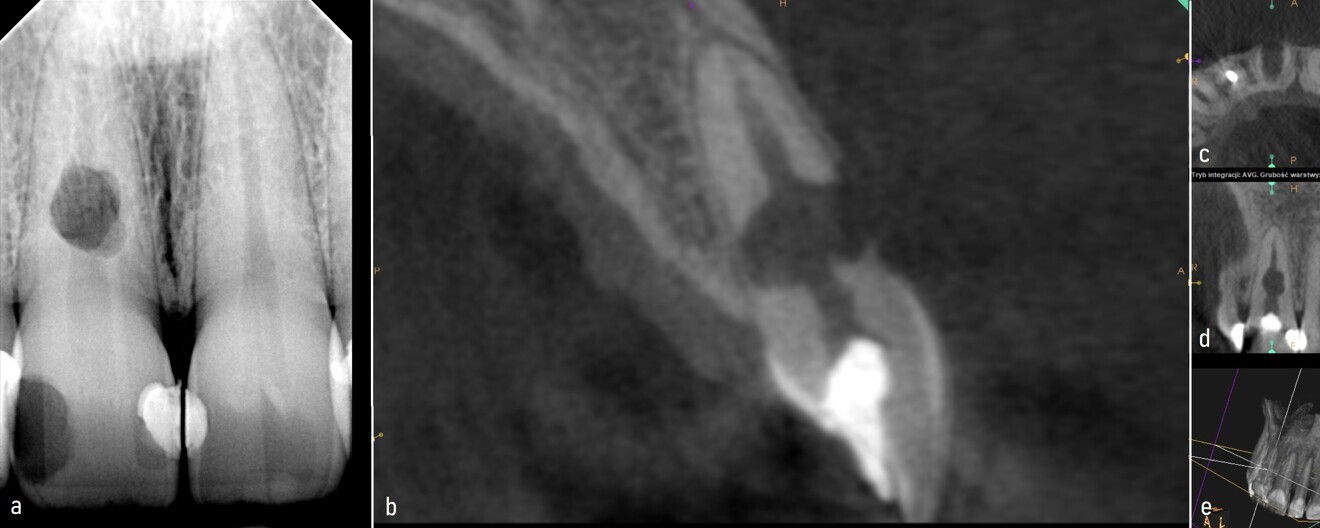

Case 1—Figs. 1a–c: CBCT scan taken before the treatment. Axial plane showing the root wall perforation (a). Coronal plane showing the lesion (b). Sagittal plane showing the perforation of the cortical bone (c).

A 40-year-old female patient was referred to the endodontic office because of an incidental finding of IRR in the maxillary left lateral incisor on a panoramic radiograph. A CBCT scan was taken to assess the extent of the resorption, devise a treatment plan and determine the prognosis (Figs. 1a–c). The resorption cavity was located in the middle of the root and had perforated the mesial wall of the root. The rather round and regular shape of the resorption indicated the inflammatory type. The osteolytic focus suggested a lesion was present next to the perforation area (Fig. 2). Owing to the size of the wall perforation and the presence of the lesion, the treatment plan involved a single-session root canal treatment as well as a surgical approach.